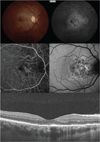

Results: The median (range) age at presentation was 31 (27-52) years. The median (range) interval between symptom onset and presentation was 4 (1-20) weeks. Associated systemic findings included a viral prodrome (50%), orchitis (50%), hand-foot-mouth disease (25%), and positive coxsackievirus titers (50%). The median (range) visual acuity at initial examination was 20/400 (20/70 to 1/400), which improved to 20/30 (20/20 to 20/60) at final follow-up. The median (range) follow-up time was 8 (8-13) weeks. Early in the disease course, the central macula developed irregular, circular areas of white-gray discoloration. Following recovery, the macula had a stippled retinal pigment epithelium characterized by rarefaction and hyperplasia. Fluorescein angiography demonstrated irregular early hyperfluorescence and late subretinal hyperfluorescence. Spectral-domain optical coherence tomography showed a partially reversible disruption of the outer photoreceptor layer. Fundus autofluorescence initially revealed stippled autofluorescence that eventually became more hypoautofluorescent. Indocyanine green angiography showed "moth-eaten"-appearing choroidal vasculature, suggestive of choroidal inflammation.

Conclusions: The imaging characteristics highlight the structural changes during the active and resolution phases of unilateral acute idiopathic maculopathy. The visual recovery correlates with structural changes and suggests that the pathogenesis involves inflammation of the inner choroid, retinal pigment epithelium, and outer photoreceptor complex that is partially reversible.